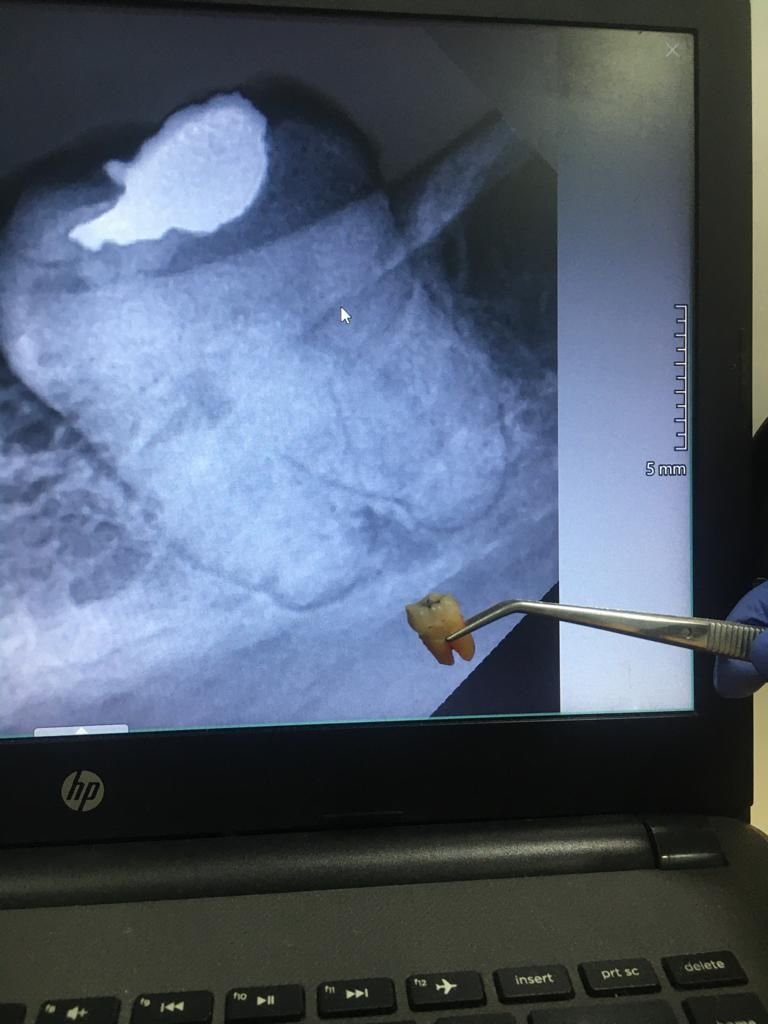

4. Pengangkatan gigi

Bila gigi sulit dicabut, dokter membaginya menjadi beberapa bagian lalu mengangkat potongan satu per satu.

Dokter melakukan rontgen panoramic untuk melihat posisi gigi bungsu dan menilai kondisi pasien.